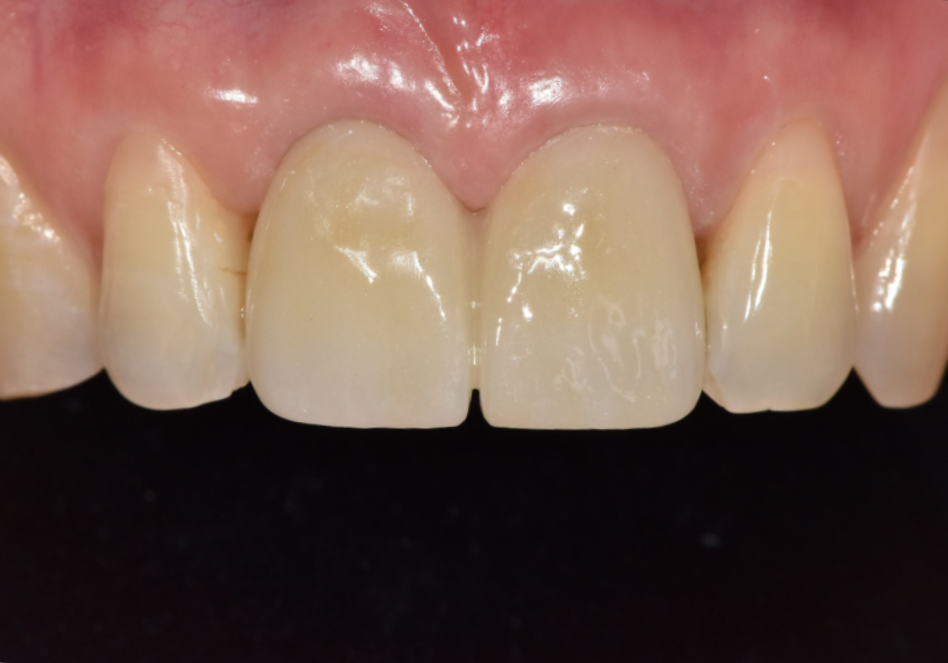

오래전 씌운 치아, 잇몸이 까매져 내원한

환자분 사례

잇몸 까매짐 원인,증상,치료 방법

이 환자분은 오래 전에

앞니 2개(#11, #21)와

윗니 어금니 1개(#15)에

PFM 크라운을 씌우셨다고 합니다.

250513

그런데 시간이 점점 지나면서

잇몸이 까매지더니

요즘엔 냄새까지 난다며

걱정스러운 표정으로 내원하셨습니다.

최종 보철 제작

이후 최종 보철물을 제작해서 부착했고,

환자분은 잇몸 색도 자연스럽게 회복되고

냄새도 사라졌다고 하셨습니다.